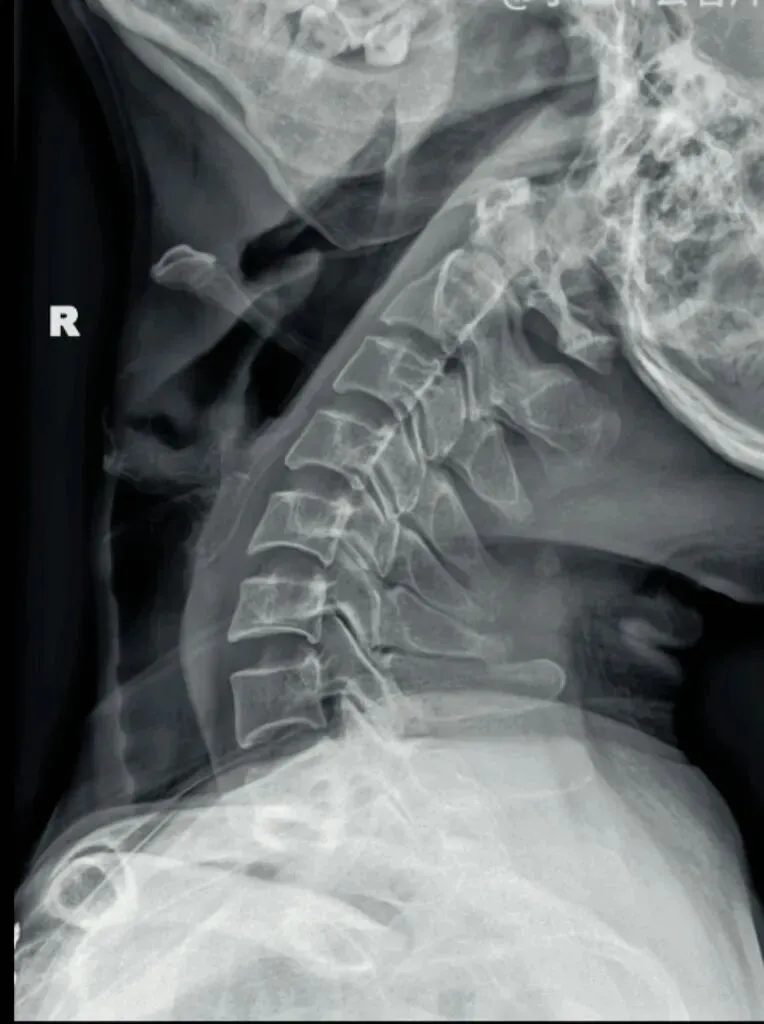

一骨是是我们主要在颈椎侧位X线片中观察椎体的形态与结构,查看椎体是否规则,

椎体边缘有无变尖或呈唇样改变的骨质增生。

椎体骨质有无破坏,密度是否正常,如肿瘤或者感染。

椎体的高度是否均匀,有无压缩变形。椎体高度减小可能提示骨质疏松、压缩性骨折

或椎体的发育异常等。